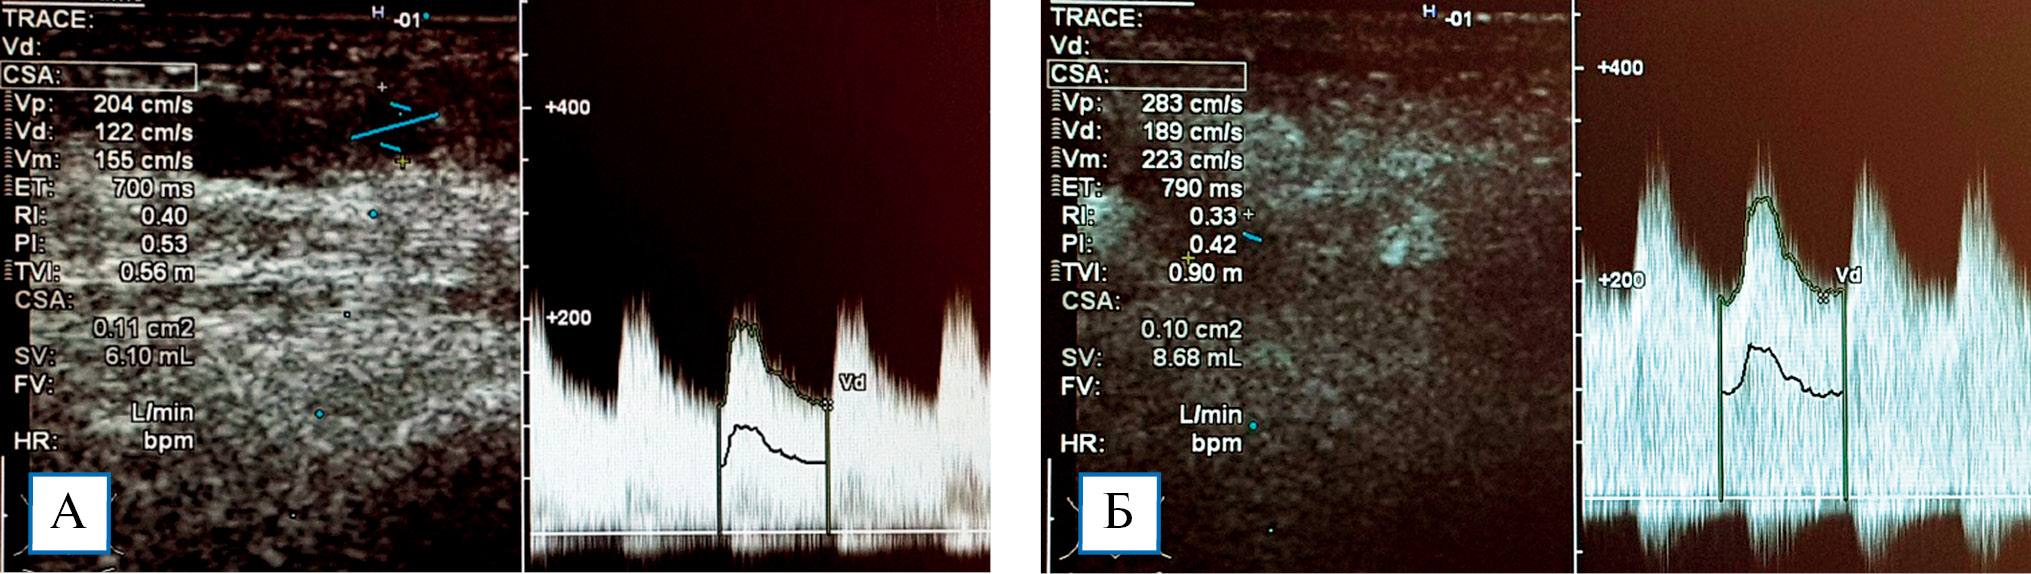

При пробе с физической нагрузкой у пациентов без стил-синдрома наблюдалось увеличение показателя ОСК на 29,3 ± 4,6% (рис. 3). Снижение тонуса резистивных сосудов при физической нагрузке способствует увеличению притока крови в микроциркуляторное русло кисти, что является важным механизмом ауторегуляции кровотока и адаптации к гипоперфузии. При стил-синдроме в ответ на физическую нагрузку реакция отсутствовала, что указывает на срыв компенсаторных механизмов регуляции кровотока в кисти (рис. 4).

Рис. 3. Эхограммы локтевой артерии: объемная скорость кровотока исходно (А) составила 610 мл/ мин, после пробы с физической нагрузкой (Б) — до 868 мл/мин (увеличение на 30,0%)

Рис. 4. Эхограммы локтевой артерии: объемная скорость кровотока исходно составила 425 мл/мин (А), ее снижение после пробы с физической нагрузкой до 417 мл/мин свидетельствует о срыве компенсаторных механизмов ауторегуляции кровотока в кисти (Б)